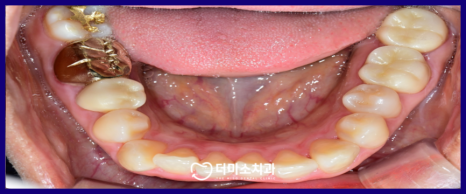

오늘은 보철치료를 받은

치아의 잇몸 라인이 검게 비춰 보여

광명동치과 더미소치과를

내원해 주신 환자분의 사례를 통해

재신경치료에 대해

더 자세히 알려드리겠습니다.

오늘 소개해 드릴

환자분께서는 30대 여자분으로

타 치과에서 신경치료와

크라운 수복 치료를 받은 후

잇몸라인이 검게 비춰보여

심미적으로 불만족하신다며

검사를 위해 본원을 내원해 주셨는데요.

환자분께서는

눈에 거슬렸던 까만 부분이 사라져

만족해하셨으며,

처음 내원 당시 보다 보철물이

훨씬 더 주변 치아와 조화를 잘 이루고

심미성이 뛰어나 만족해하셨습니다.